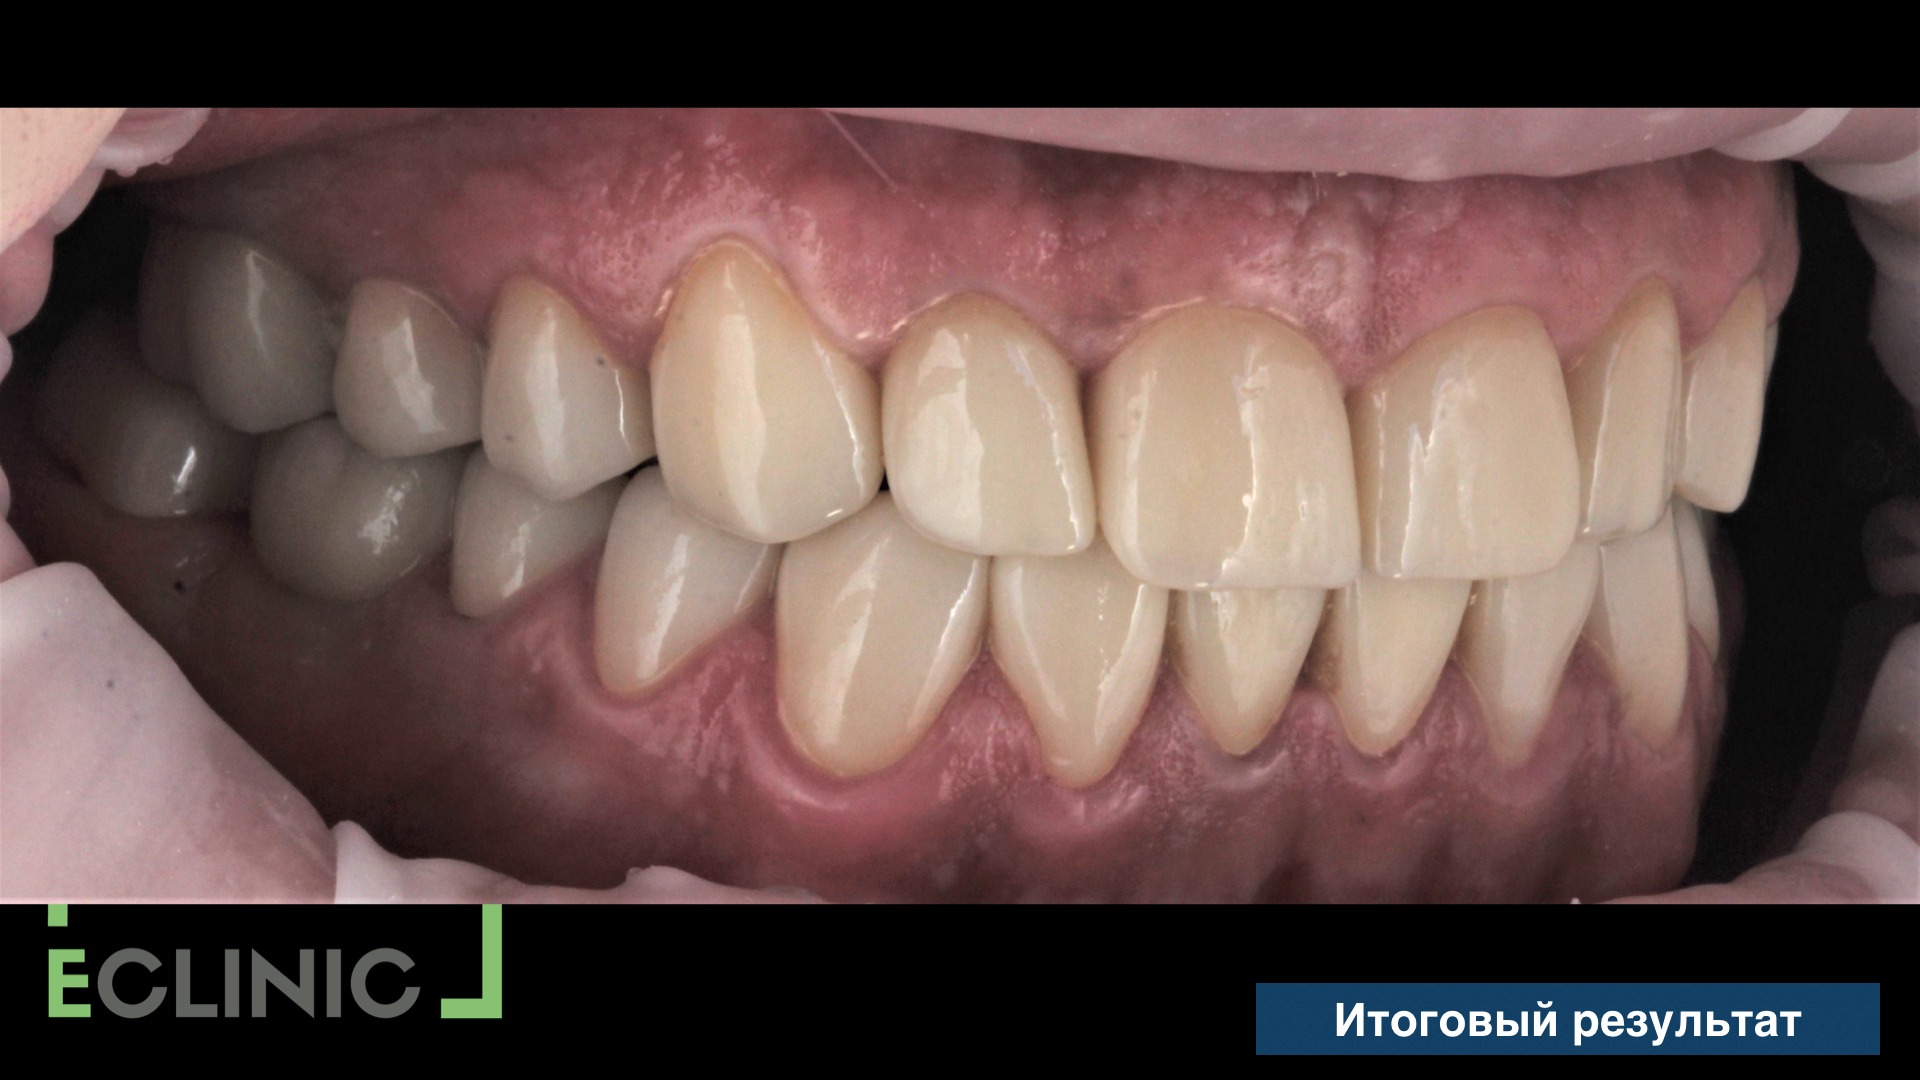

Нашим ортодонтом был собрана система для интрузии (внедрения) зуба 47 и, после 3 месяцев, мы завершили протезирование, установив две последние коронки.